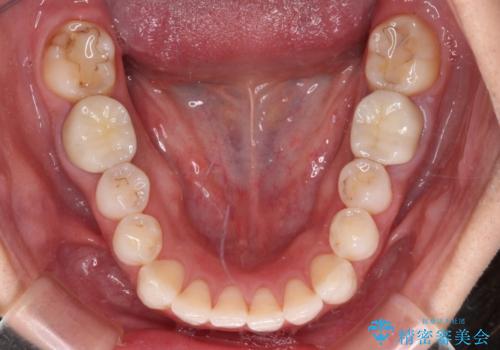

口腔内から、土台も含め銀歯がなくなったことでメタルフリーとなりました。